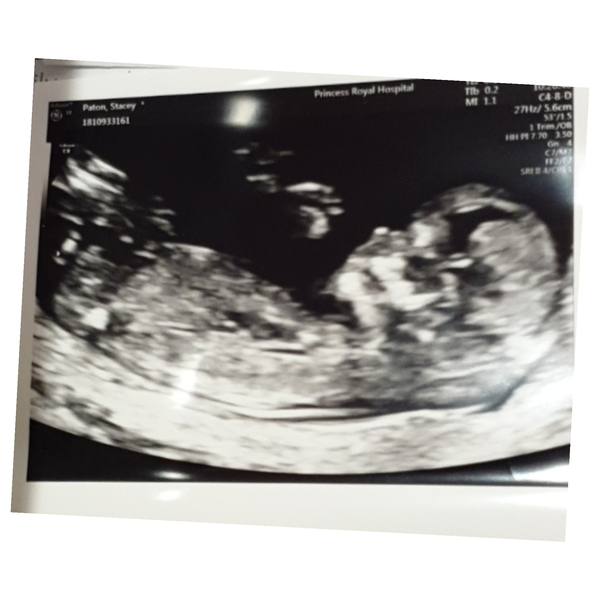

Hi everyone Scan went well baby looks perfect measuring at 12+1 so due 23rd of July! Was amazing seeing how much they have grown since the little blob at 8 weeks! Hope you are all well xx

@Jackgordonsmummy what a fab scan picture! So clear! Delighted everything went well for you! I can't wait to reach the same milestone. Are you going to tell people now or still hang off for a while? Xx